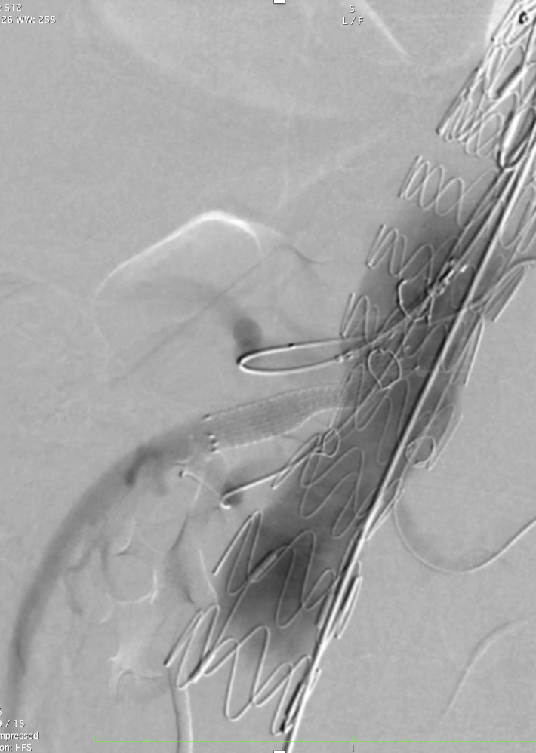

超选SMA,桥接8-100mm Viabahn,内衬8-60mm Absolute裸支架

超选CA,桥接8-100mm Viabahn

超选RRA烟囱支架,桥接6-100mm+6-50mm Viabahn

超选LRA烟囱支架,桥接6-100mm Viabahn

术后造影